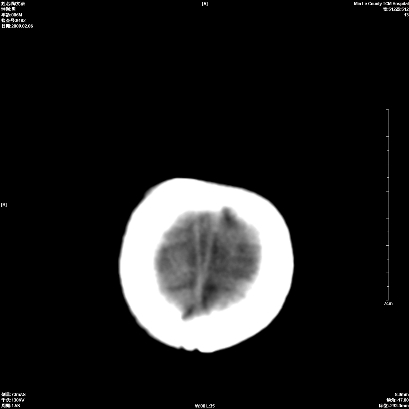

以下是引用wxq2008在2009-2-6 17:01:00的发言:[br]hie后遗症脑萎缩。

以下是引用学医在2009-2-6 21:45:00的发言:[br]hie后遗改变